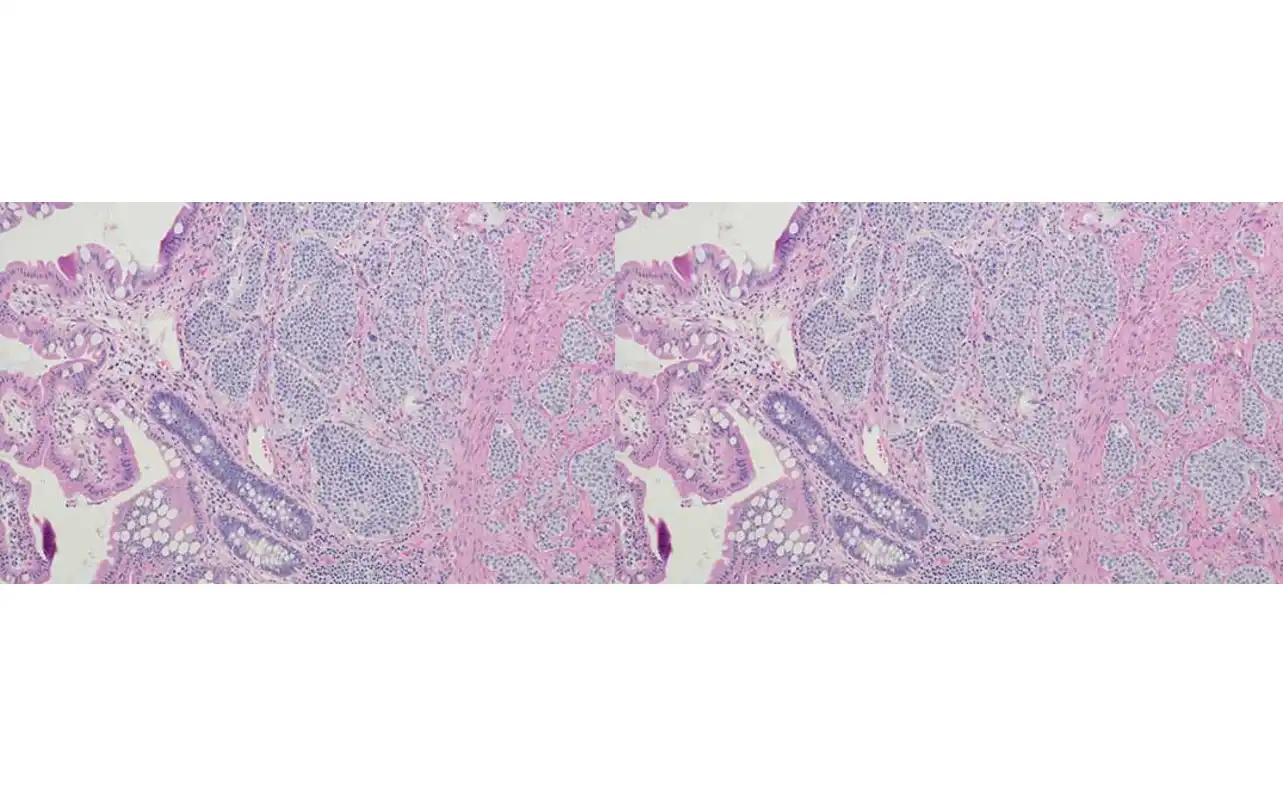

A small sample of tissue is taken and examined under a microscope to confirm the presence of cancer cells.